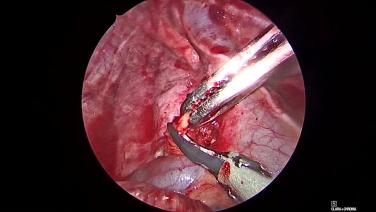

Thorascopic Lobectomy - Dissect Out & Encircle Pulmonary Artery